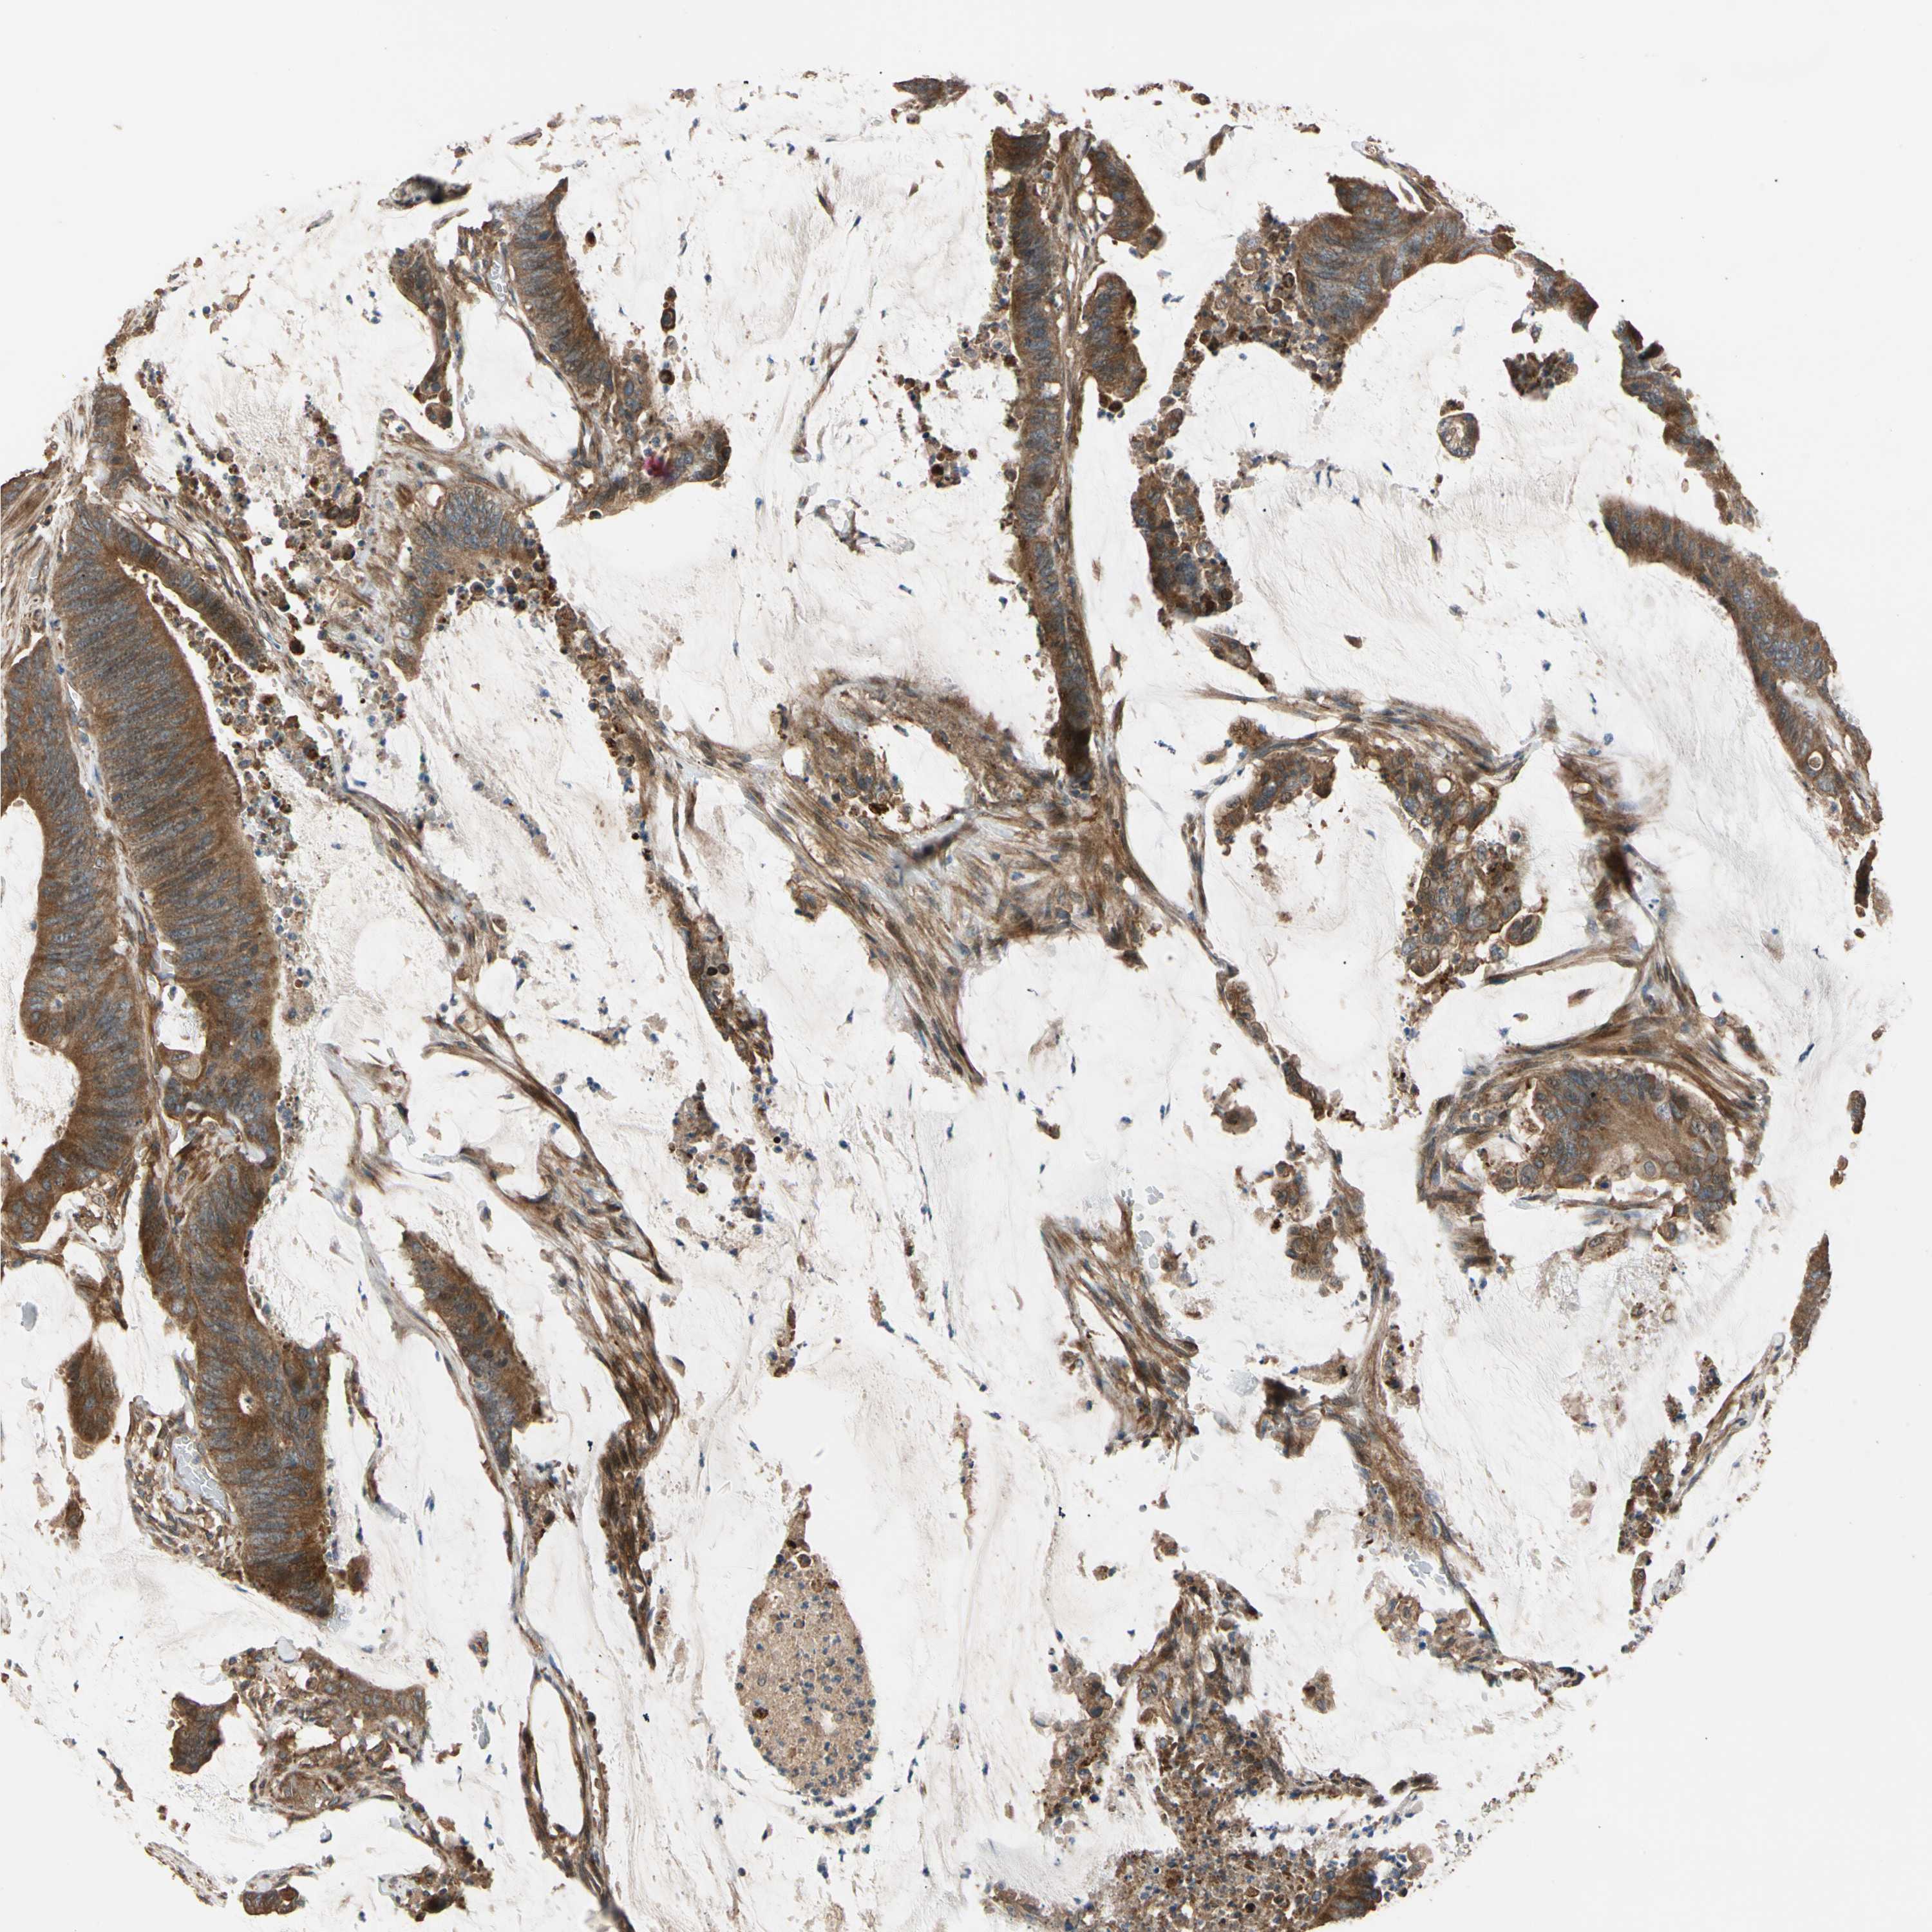

CANCER COLORECTAL CANCER Show tissue menu

Colorectal cancer

Human cancer

Colon adenocarcinoma